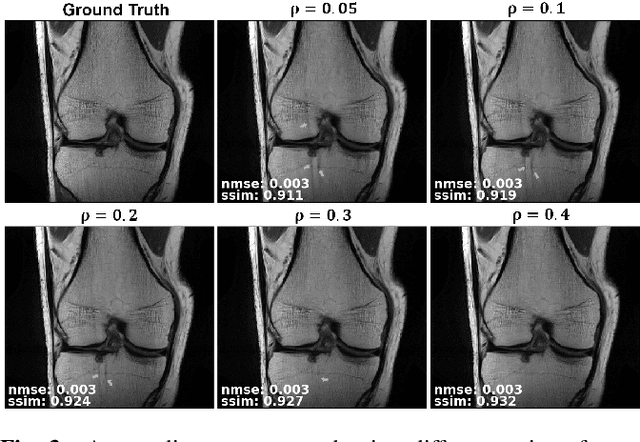

Abstract:Purpose: To develop a strategy for training a physics-driven MRI reconstruction neural network without a database of fully-sampled datasets. Theory and Methods: Self-supervised learning via data under-sampling (SSDU) for physics-based deep learning (DL) reconstruction partitions available measurements into two sets, one of which is used in the data consistency units in the unrolled network and the other is used to define the loss for training. The proposed training without fully-sampled data is compared to fully-supervised training with ground-truth data, as well as conventional compressed sensing and parallel imaging methods using the publicly available fastMRI knee database. The same physics-based neural network is used for both proposed SSDU and supervised training. The SSDU training is also applied to prospectively 2-fold accelerated high-resolution brain datasets at different acceleration rates, and compared to parallel imaging. Results: Results on five different knee sequences at acceleration rate of 4 shows that proposed self-supervised approach performs closely with supervised learning, while significantly outperforming conventional compressed sensing and parallel imaging, as characterized by quantitative metrics and a clinical reader study. The results on prospectively sub-sampled brain datasets, where supervised learning cannot be employed due to lack of ground-truth reference, show that the proposed self-supervised approach successfully perform reconstruction at high acceleration rates (4, 6 and 8). Image readings indicate improved visual reconstruction quality with the proposed approach compared to parallel imaging at acquisition acceleration. Conclusion: The proposed SSDU approach allows training of physics-based DL-MRI reconstruction without fully-sampled data, while achieving comparable results with supervised DL-MRI trained on fully-sampled data.